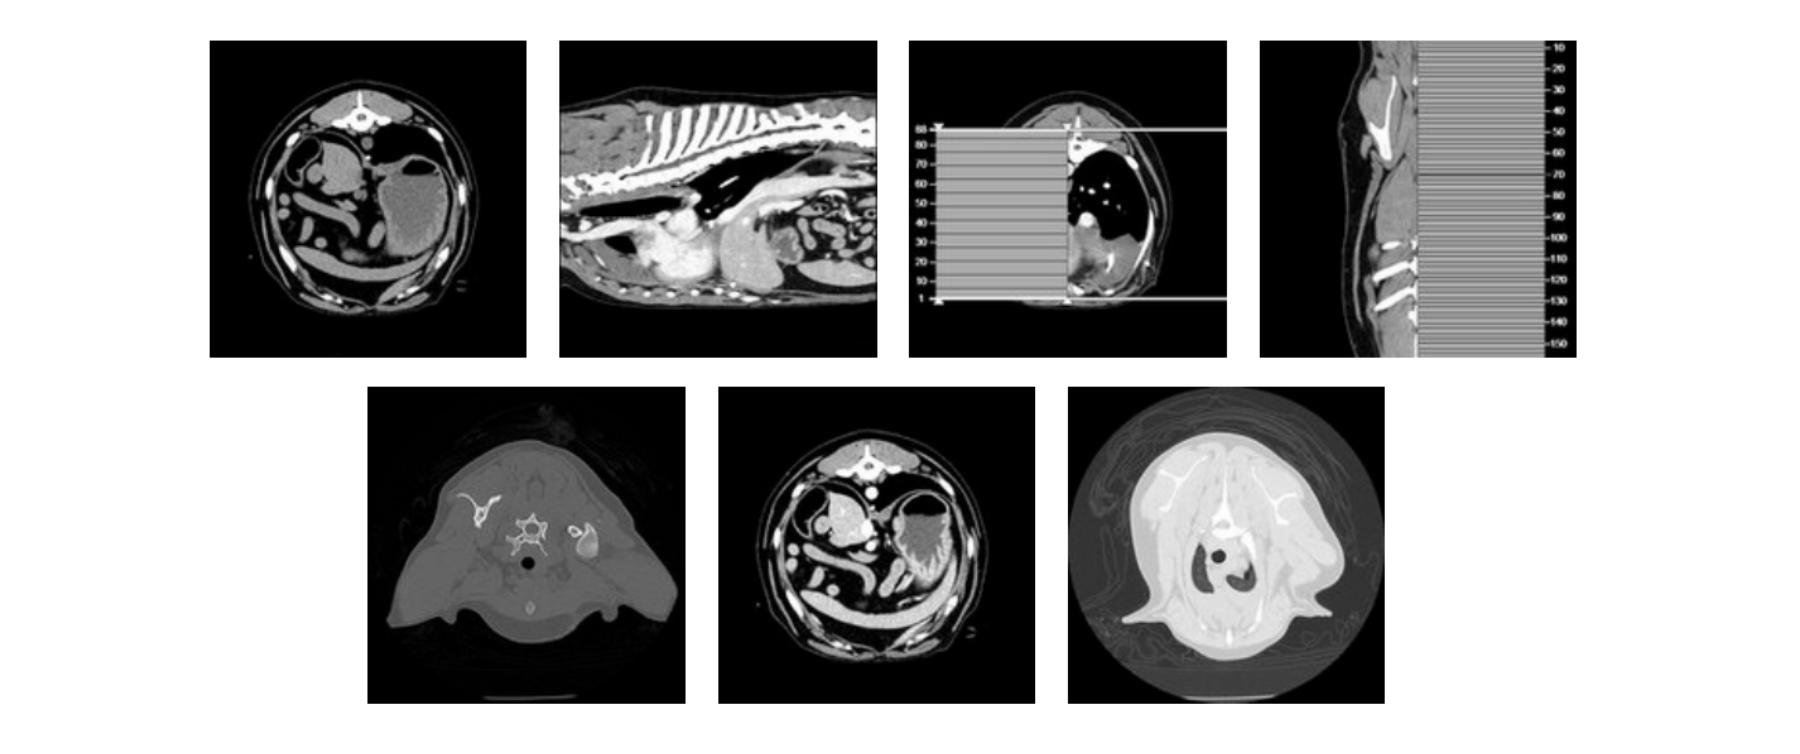

Thoracic CT Scan (05-29-2024):

Findings: While the CT scan focused our attention on the cranial mediastinum, the quills themselves were not apparent on the imaging. This ambiguity necessitated a comprehensive approach to ensure that no lung area, left or right, was overlooked.

Interpretation: The CT findings were critical in guiding the decision for surgical exploration, leading to the choice of a median sternotomy to access the entire chest space for thorough examination and treatment.